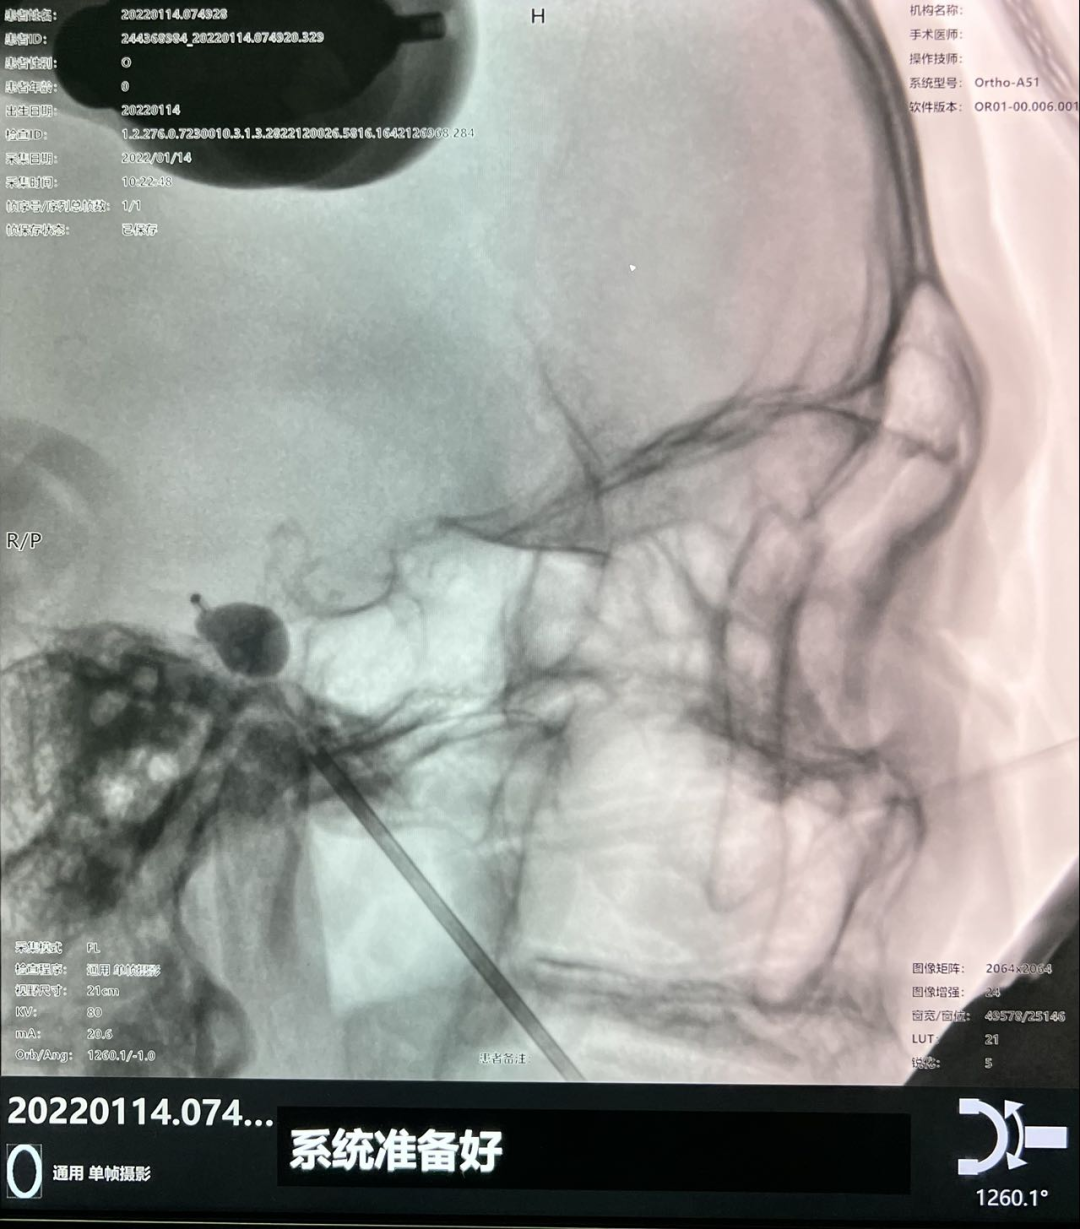

图1 术前通过机器人手术计划系统

设计术中穿刺路径及靶点

图2 术前在机器人辅助下定位穿刺点

但该患者手术需要精确的三维定位,术中需把穿刺针准确穿入皮下约8cm深、直径仅为3mm左右的卵圆孔,传统方法只能在C型臂引导下徒手穿刺,一次性穿刺成功率低。如何高效率穿刺成功,从而减少患者术中风险成为了迟令懿团队亟待解决的问题。在神经外科副主任李卫国的指导下,迟令懿采用机器人辅助立体定向下穿刺。术前验证误差仅为0.3mm,术中仅用10秒钟即完成了穿刺操作,避免了反复穿刺导致的血管、组织损伤,减少了C型臂透视的次数,降低了手术风险和并发症。术后,患者面部疼痛即刻消失,1天后顺利出院。

图3 术中在机器人辅助下穿刺并置入球囊